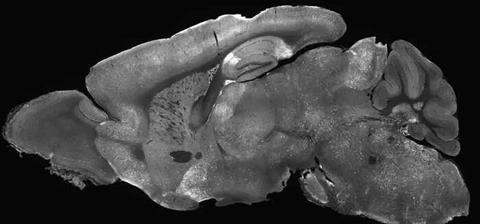

Mouse brain image glowing with experimental gene supplementation therapy highlighting how AAV delivers treatment across the entire brain. Credit: Allen Institute/Andrew Clark[/caption]